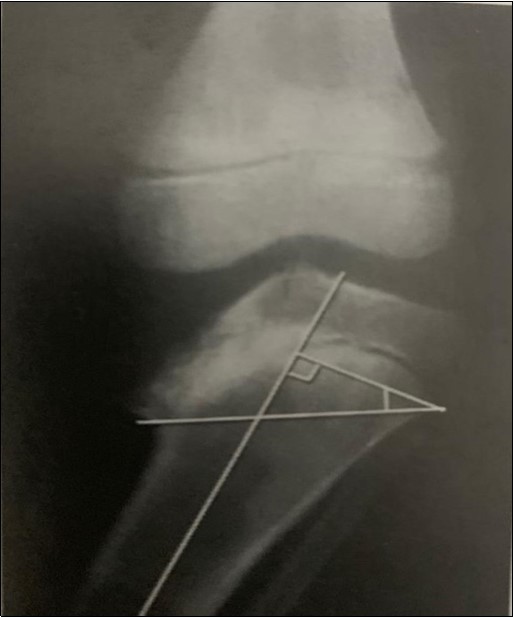

Weight-bearing radiographs are taken in the anteroposterior and lateral projections of the lower limbs in a standardized form.The disease can be classified using Langenskiold classification system, Figure 1, 12.

Figure 1.Langenskiold staging describes six radiographic stages of the disease based on the degree of epiphyseal depression and metaphyseal fragmentation of the proximal medial tibial epiphysis 13.

Langenskiold staging describes six radiographic stages of the disease based on the degree of epiphyseal depression and metaphyseal fragmentation of the proximal medial tibial epiphysis 13.

Figure2 depicts the measurement of the metaphyseo-diaphyseal angle which is another method for classifying the disease. A line is drawn perpendicular to the long axis of the tibia and another across the metaphyseal flare. The acute angle formed by these two lines should normally not exceed 11 degrees 7.

Figure 2.These classification systems are employed to aid diagnosis, monitor progression and to guide treatment of the disease 13

These classification systems are employed to aid diagnosis, monitor progression and to guide treatment of the disease 13

The metaphyseo-diaphyseal angle (MDA) better correlates with treatment outcomes as compared with the Langenskiold classification system 14.